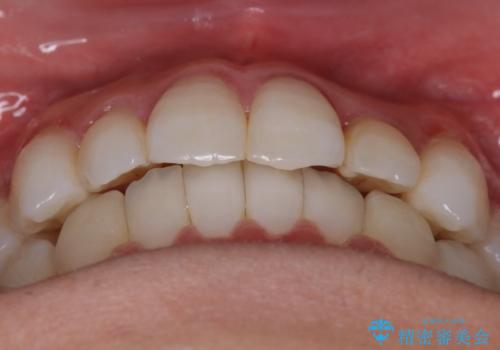

【非抜歯】八重歯を治す マウスピース矯正

- 前歯のガタつきの治療を主訴にご来院されました。

目立たない装置をとのご要望があったため、検査結果をふまえてインビザラインでの非抜歯矯正を行うこととなりました。

非抜歯での治療

抜歯をせずに歯のガタつきを治すためのスペースを作るために

①歯の遠心移動

②歯列弓の拡大

③IPR(歯を少し小さく削る)

この3つの方法を複合的に組み合わせて治療を行いました。

抜歯をせずとも笑った時の歯の見え方が劇的に変化していることが分かります。